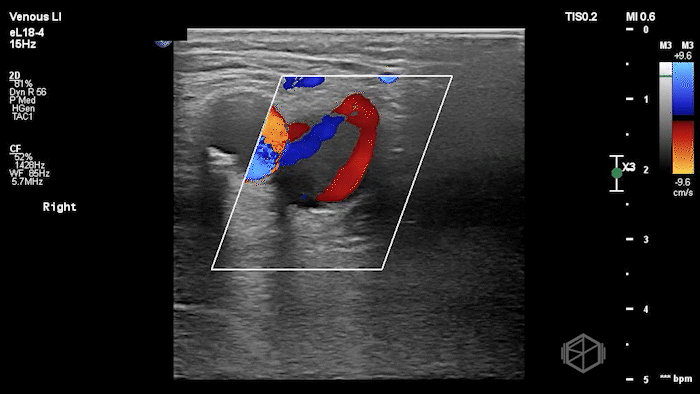

A lower extremity DVT ultrasound performed by Dr. Koutsounadis demonstrated the following:

The POCUS shows a right common femoral vein thrombus. Family members reported that the patient had previously been diagnosed with a DVT very recently and was on apixaban.

The thrombus appeared predominantly hypoechoic to nearly anechoic, making it difficult to appreciate on B-mode imaging alone. However, incomplete compressibility of the vein confirmed the presence of thrombus.

Diagnosis: Right common femoral partially occlusive DVT